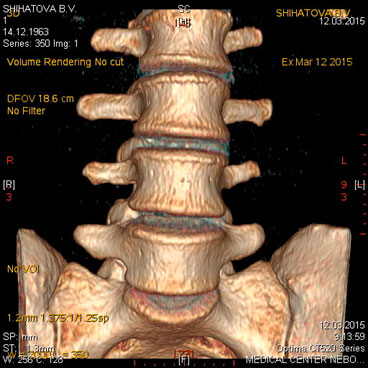

МСКТ позвоночника и спинного мозга.

Метод МСКТ очень ценен для выявления дегенеративно-дистрофических изменений, диагностируются грыжи дисков и элементы, суживающие позвоночный канал. МРТ превосходит визуализацию спинного мозга, содержимое дурального мешка, возможность увидеть другие уровни. Однако для пациентов с типичным течением болезни локализацией симптомов на одном уровне с одной стороны МСКТ обычно достаточна для постановки диагноза.

Показания:

- подозрение на опухолевое, метастатическое поражение с деструкцией

- травматическое поражение

- подозрение на грыжу диска (с обязательным указанием сегмента поражения) при невозможности проведения МРТ

- воспалительные процессы (специфические и неспецифические) с деструкцией костных структур

Подготовка: не требуется. Предварительное рекомендуемое обследование: заключение невролога